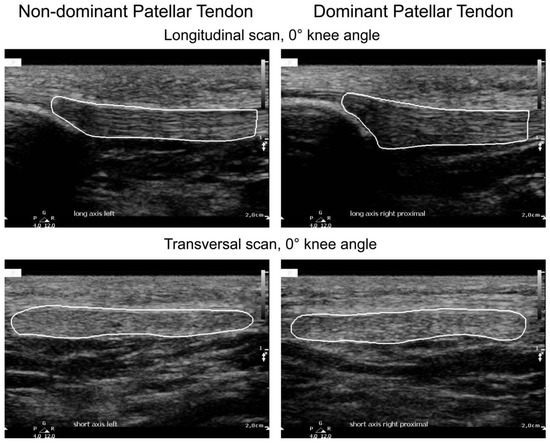

2.2. Ultrasound Image Acquisition and Protocol

| Plane | Probe Position | Knee Angle |

|---|---|---|

| Transversal | Proximal | 0° |

| Longitudinal | Proximal | 0° |